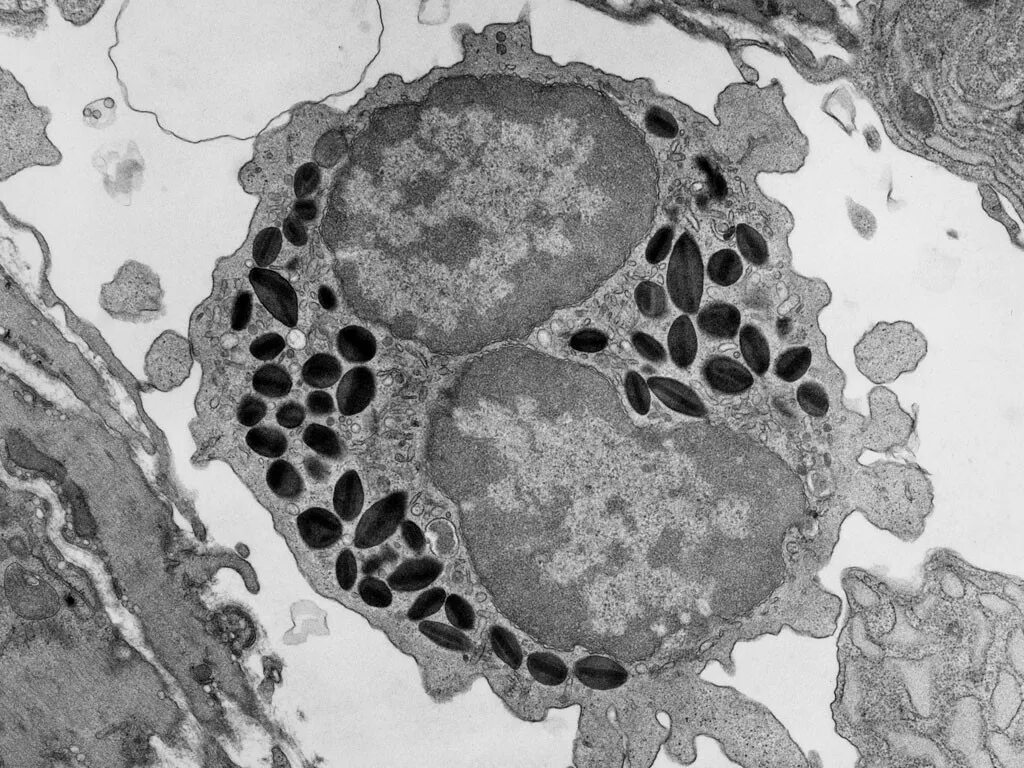

Эозинофилы гистология